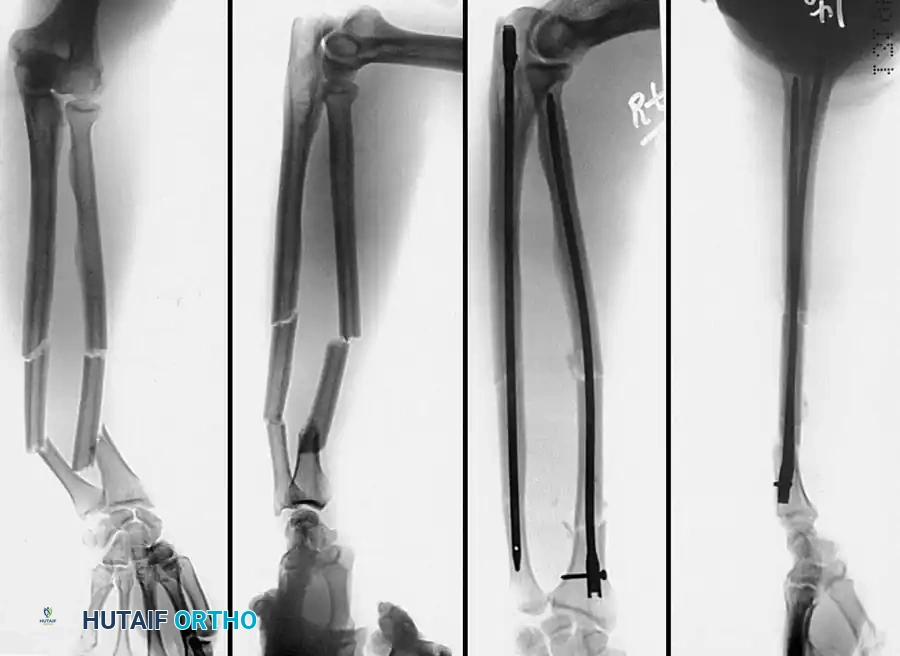

2. Intramedullary Fixation with Tension Band

If the fracture is more distal, or if there is a tendency for the proximal fragment to angulate posteriorly, a simple tension band wire is insufficiently stable. In these cases, intramedullary fixation (using Kirschner wires or a large cancellous screw) is combined with the tension band.

Kirschner Wires vs. Cancellous Screws:

* K-wires: The AO technique utilizes two parallel K-wires (1.6 mm or 2.0 mm) driven down the medullary canal. To prevent proximal migration, the K-wires must engage the anterior cortex of the ulna distal to the coronoid.

* Cancellous Screw: A biomechanical analysis by Murphy et al. demonstrated that a long 6.5-mm or 7.3-mm AO cancellous screw combined with a figure-of-eight wire provides a significantly stronger construct than K-wires. The screw must be long enough to achieve secure purchase in the ulnar diaphysis.

Fig. 54-55 Olecranon fracture repaired with long 6.5-mm AO cancellous screw and figure-of-eight tension band wire loop. Screw must engage cortex of diaphysis of ulna.